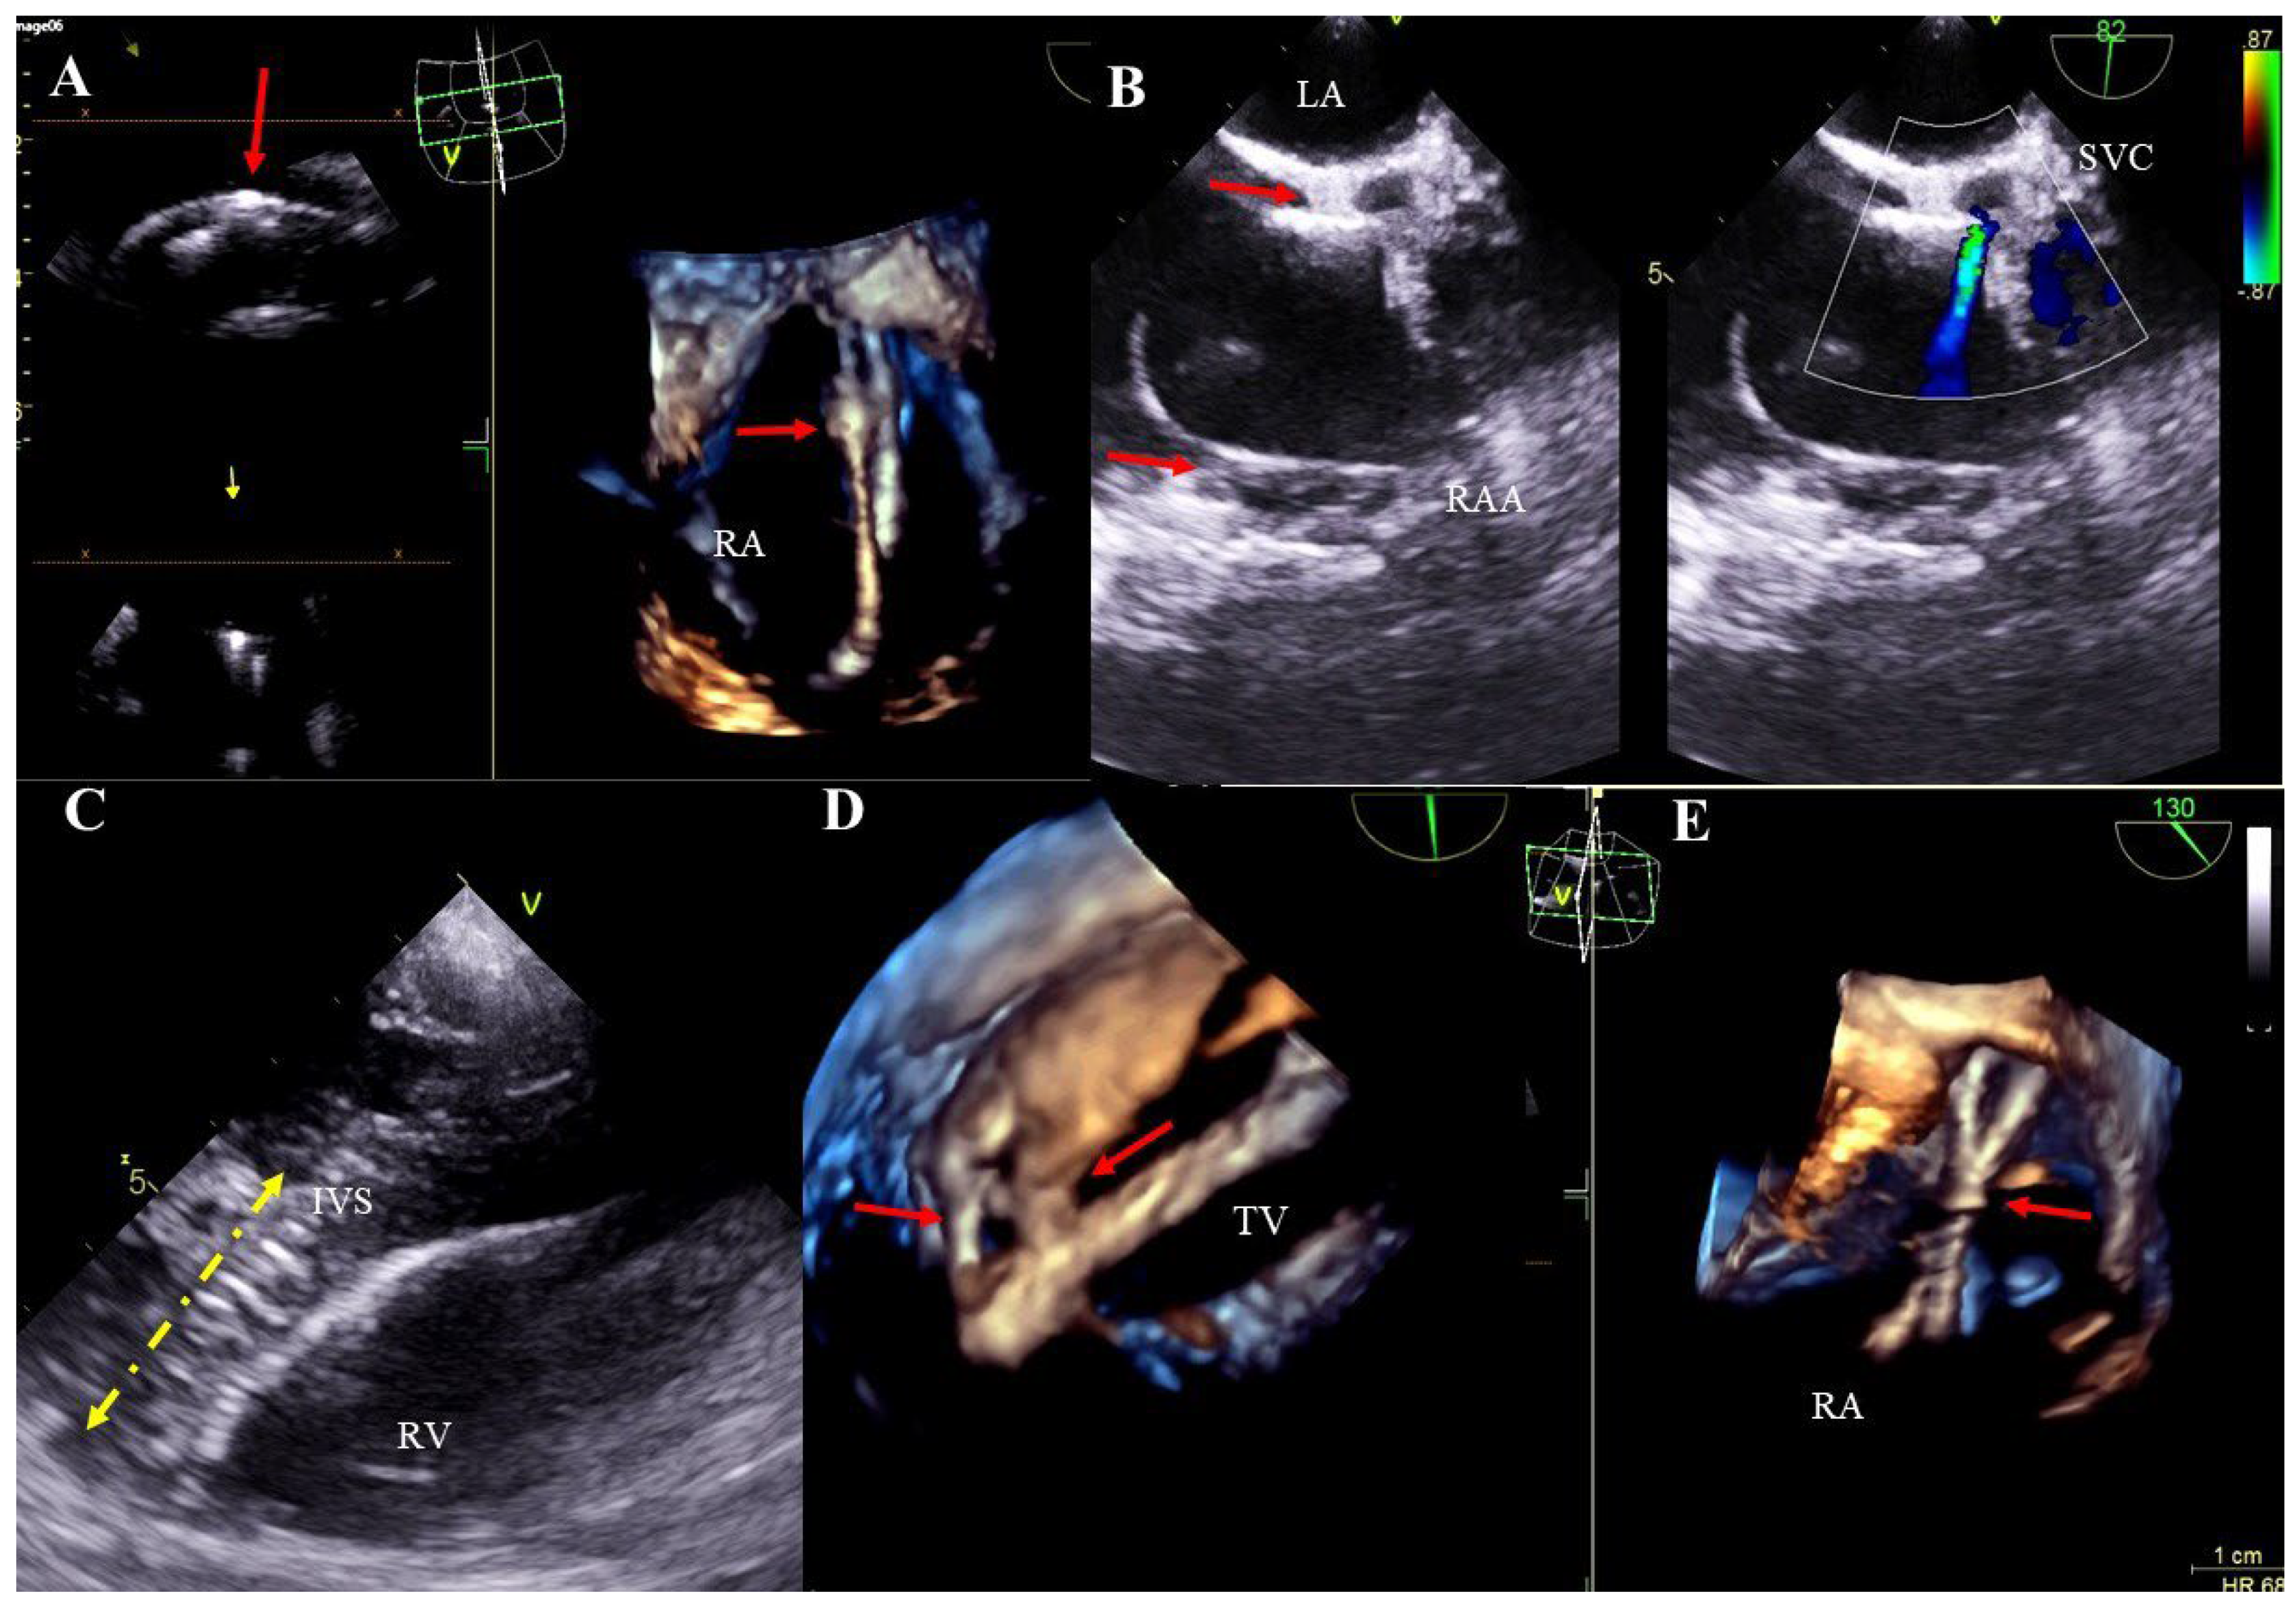

Lead thickening: segmental thickening and hyperechogenicity caused by the presence of scar tissue. Additionally, uneven outlines of the thickened lead segment with small mobile structures and with a consistent clinical picture may suggest an inflammatory process (Figure 3A–E, Movie S5).

Lead adhesion to surrounding structures: due to the presence of fibrous encapsulation, the lead adheres to the anatomical structures of the heart or the vein wall (Figure 3B–D, Movie S6). A characteristic feature is the joint movement of the bound elements. The term also includes lead-on-lead adhesions (two or three leads) that move together (Figure 3A,E, Movie S5). Attached masses binding the lead to the surrounding structures (vein wall or heart structures) are remnants of a previous asymptomatic inflammatory response to the presence of the lead in the heart. Over time, they may calcify or mineralize, crystallize or even ossify.

Figure 3. TEE (2D, 3D) showing scar tissue around the leads. Segmental thickening of the leads and lead-on-lead adhesions in the right atrium (red arrow) (A). Pathological attachment of the two leads to the interatrial septum and to the atrial wall near the atrial appendage (red arrows). The narrowing of the vena cava at entry into the atrium is caused by the thickened leads and pathological scar tissue (Doppler color) (B). Thickened ventricular lead (yellow line) pathologically attaches to the endocardium of the interventricular septum in the right ventricle (C). The image from the right ventricle depicts a pathological adhesion (red arrows) of the lead to the edge of the tricuspid valve leaflet (D). Binding and intersection of thickened leads in the atrium (red arrow) (E).